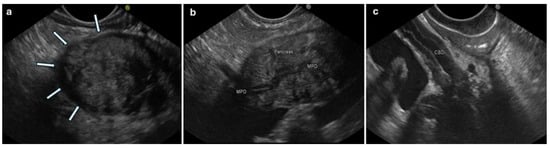

- Palazzo, M.; Palazzo, L.; Aubert, A.; Fabre, M.; Couvelard, A.; Vullierme, M.-P.; Maire, F.; Lévy, P.; Ruszniewski, P. Irregular narrowing of the main pancreatic duct in association with a wall thickening is a key sign at endoscopic ultrasonography for the diagnosis of autoimmune pancreatitis. Pancreas 2015, 44, 211–215. [Google Scholar] [CrossRef]

- Koyama, R.; Imamura, T.; Okuda, C.; Sakamoto, N.; Honjo, H.; Takeuchi, K. Ultrasonographic imaging of bile duct lesions in autoimmune pancreatitis. Pancreas 2008, 37, 259–264. [Google Scholar] [CrossRef] [PubMed]

- Kubota, K.; Kato, S.; Uchiyama, T.; Watanabe, S.; Nozaki, Y.; Fujita, K.; Yoneda, M.; Inamori, M.; Shimamura, T.; Abe, Y.; et al. Discrimination between sclerosing cholangitis-associated autoimmune pancreatitis and primary sclerosing cholangitis, cancer using intraductal ultrasonography. Dig. Endosc. 2011, 23, 10–16. [Google Scholar] [CrossRef] [PubMed]

| Gland volume: diffuse enlargement | Gland volume: focal enlargement (within the pancreatic head in about 2/3 of cases) [37] | Caliber: dilated. | Wall: thickened. | Volume: enlarged (≥8 mm) [48] | The loss of interface between the pancreas and vessels of the portal system and potentially others [48] |

| Echotexture: diffuse hypoechogenicity, diffuse hypoechoic areas | Echotexture: focal or diffuse hypoechogenicity [48] | Wall: regular homogenous thickening typically with a hyper–hypo–hyperechoic series of layers (“sandwich pattern”) or parenchymal echo type [62] | Echotexture: hypoechoic | ||

| MPD: hyperechoic margin [1], irregular narrowing | MPD: hyperechoic margin [1], irregular narrowing, upstream dilation [37,48] | ||||

| Peripancreatic changes: peripancreatic hypoechoic margin [37], lobular outer margin ∆ | Peripancreatic changes: lobular outer margin ∆ [37,47] | ||||